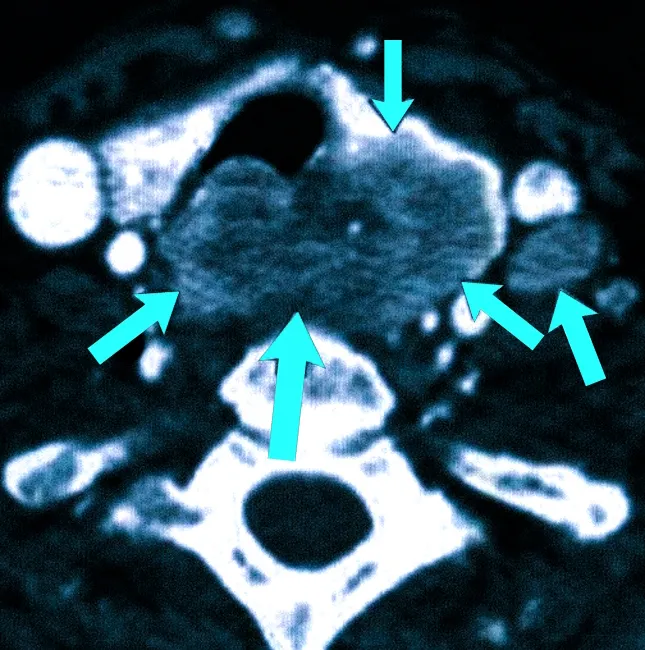

| Эхогенность | Границы между гипоэхогенными и гиперэхогенными зонами; гипоэхогенные узлы более склонны к злокачественности |

| Кальцинаты | Наличие микро- и макрокальцинатов, особенно в центре, что увеличивает риск рака |

Эти современные стандарты включают не только визуальные параметры, но и количественный анализ эхогенности, структуры и vascularisation узлов. На основе этих данных формируется так называемая "система оценки риска", которая помогает определить, сколько процентов вероятность злокачественности у конкретного узла. Это существенно повышает точность дифференциальной диагностики и помогает избежать излишних биопсий и волнений пациентов.

- Учёт не только размера, но и структурных характеристик узла, таких как плотность, эхогенность и наличие кальцинатов.

| Высокий риск | Различные признаки, такие как неровные границы, микрокальцинаты, гипоэхогенность, повышенная vascularisation, требуют биопсии |